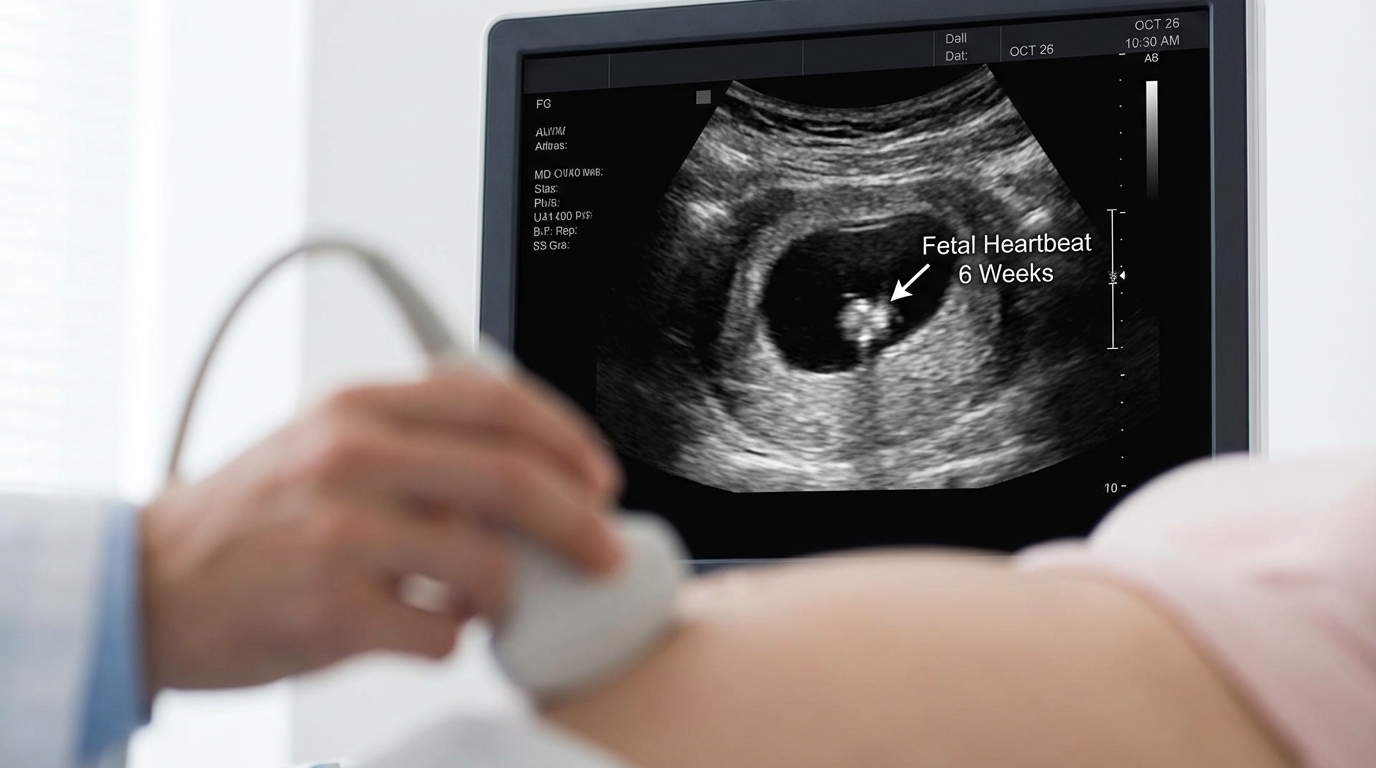

Around week 6, your doctor will schedule your first transvaginal ultrasound to confirm the embryo implanted inside the uterus and to detect cardiac activity. Seeing the heartbeat on the monitor reduces the risk of miscarriage from approximately 10% down to 3% to 5%.

ultrasound screen showing a tiny flickering heartbeat at six weeks gestation

Approximately 80% of all miscarriages occur within the first 12 weeks. The majority result from random chromosomal abnormalities in the embryo, not from anything the mother did or failed to do [4]. Once your doctor confirms a healthy fetal heartbeat on ultrasound, the statistical odds shift heavily in your favor.